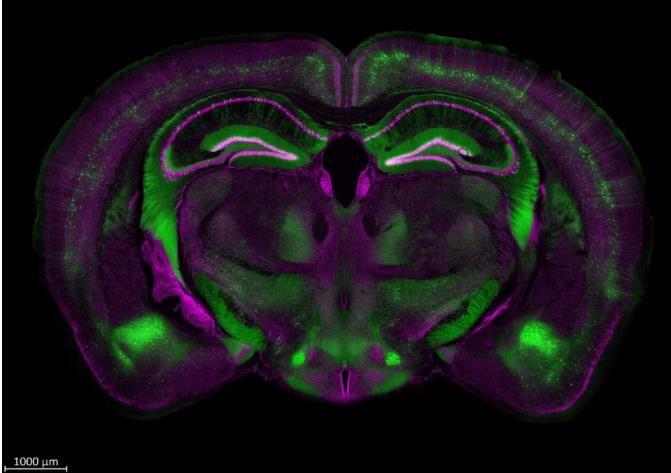

蔡司激光共聚焦顯微鏡多維成像如何設置不同的掃描策略技巧

蔡司激光共聚焦顯微鏡作為生命科學實驗最常用的儀器之一,幾乎會出現在每個生命科學研究者的“ Materials and Methods ”中。蔡司激光共聚焦顯微鏡 LSM 7/8/9 係列以其高質量的成像結果深受生命科學科研工作者的喜愛,成為了蔡司的“明星產品”。